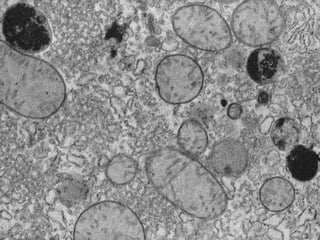

Este documento presenta imágenes microscópicas de diferentes tipos de tejidos y estructuras celulares teñidas con varios métodos histológicos. Incluye fotografías que muestran fibras de colágeno, elásticas y reticulares en diversos órganos, así como membranas basales y células especializadas de órganos como riñones, glándulas mamarias y próstata. El propósito es demostrar la aplicación de técnicas histológicas para visualizar componentes celulares y tej